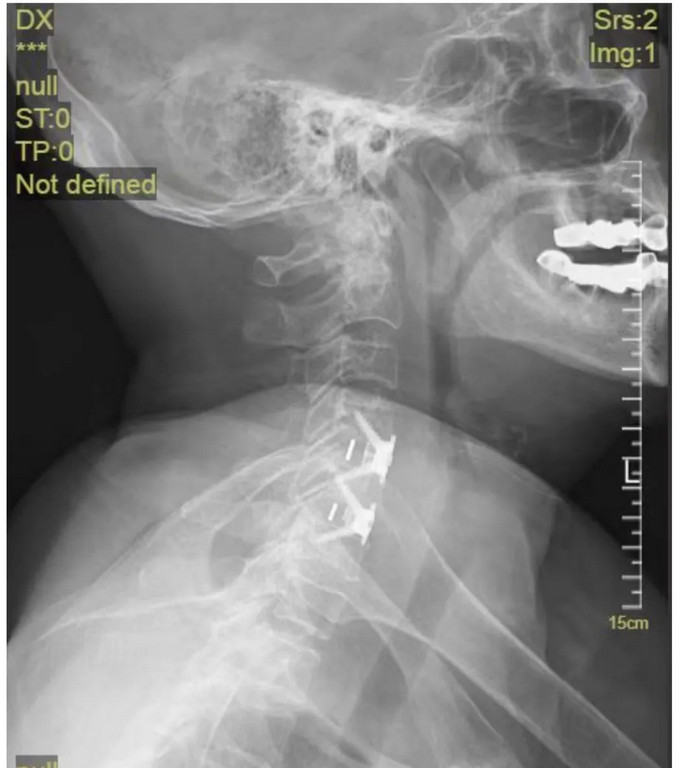

术后影像

颈椎正位DR

颈椎侧位DR